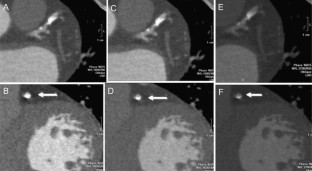

Fig. 4